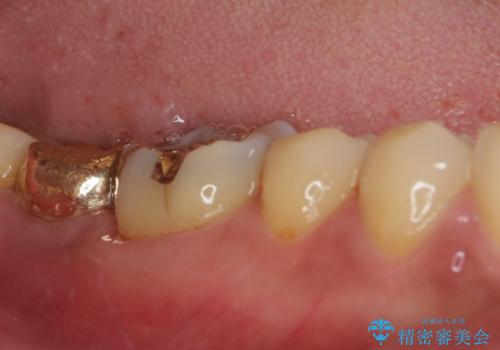

- 奥歯に装着されていたゴールドインレーが外れてしまったとのことで来院された患者様です。

外れてしまったインレーをはめたところ、インレー周辺の歯質が虫歯で失われていました。

虫歯をしっかりと取り除き、改めてゴールドインレー(PGAインレー)にて修復することとしました。